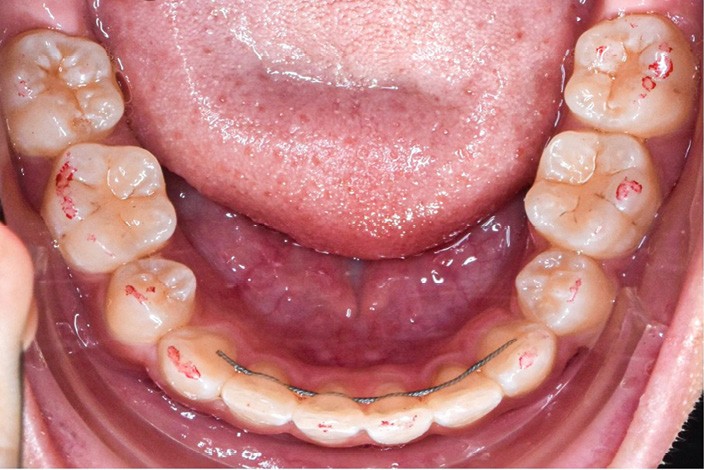

Les corrections esthétique et fonctionnelle de la canine ont été effectuées par stratifications de résine composite (fig. 13). Au préalable, une simulation numérique de la nouvelle forme à donner à la canine a été élaborée. Une fois imprimée, cette simulation a servi à fabriquer une clé en silicone moulant les faces palatines des incisives. Cette clé a été garnie d’une fine couche composite de masse « émail » (Miris, ColteneR, Suisse) qui a été polymérisée une fois replacée en bouche pour constituer une coquille palatine. Afin d’élargir légèrement le profil d’émergence, des matrices (Slick Bands Margin Elevation, Garison, R USA) ont été insérées dans le sulcus des faces proximales avant d’y fouler une fine couche de composite. La coquille a ensuite été remplie de différentes masses de composite « dentine ». Une dernière fine couche de composite de masse « émail » a finalement été appliquée en surface avant de procéder au polissage et aux finitions. Après contrôle des axes, la fermeture réciproque des espaces d’extraction s’est poursuivie. Cette phase a été suivie par les finitions, puis la dépose. Des fils collés au maxillaire et à la mandibule assurent la contention, complétés par une gouttière thermoformée maxillaire (fig. 14-20).